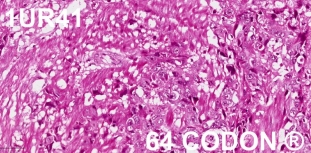

Ca. Urinary Bladder

Grade 2

Stage IIIB

pT2bN2M0